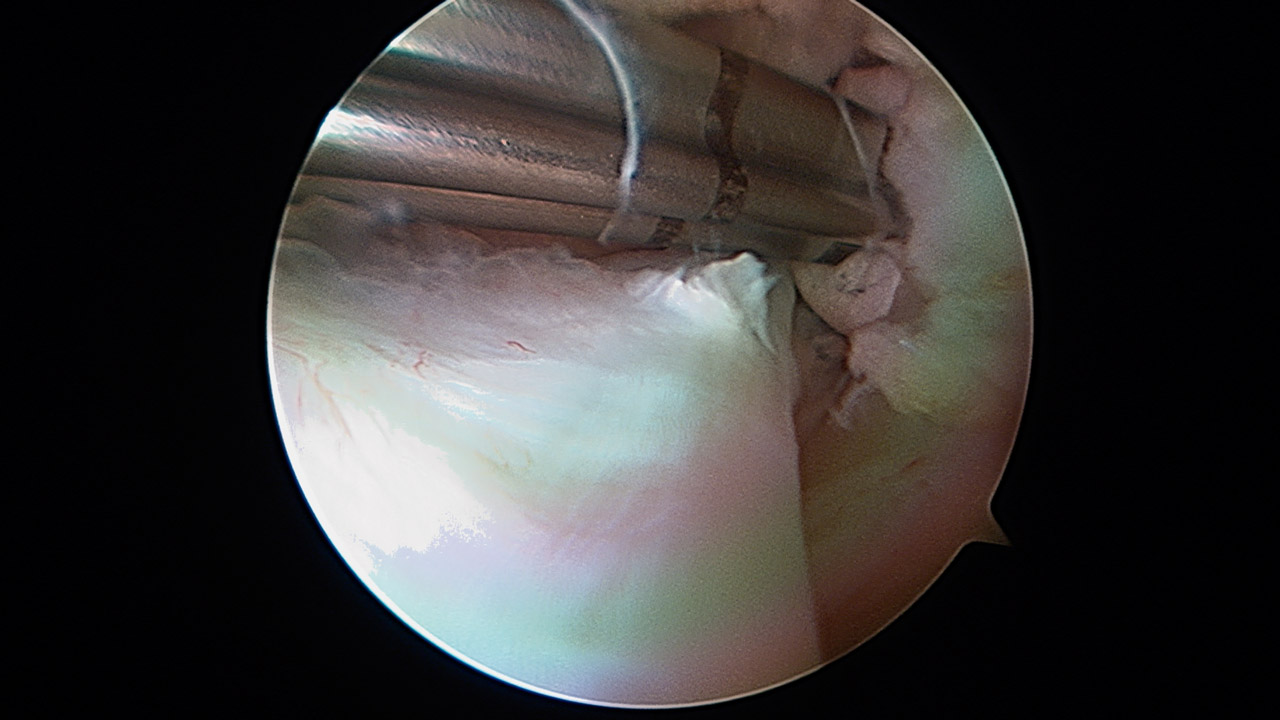

Presentamos una técnica quirúrgica artroscópica para los casos de inestabilidad traumática o atraumática de hombro, con hiperlaxitud multidireccional asociada, en los que hayan fracasado los tratamientos conservadores u otras técnicas quirúrgicas de plicatura capsular, y no presenten déficit óseo importante. Consiste en la plicatura del ligamento glenohumeral inferior (anteroinferior y posteroinferior) y la realización de una ligamentoplastia de refuerzo anterior artroscópica con aloinjerto en disposición transubescapular.

We present an arthroscopic surgical technique for cases of traumatic instability or atraumatic of the shoulder, with associated multidirectional hyperlaxity in which conservative treatments have failed, or other surgical techniques of plication capsular, and do not present major bone deficits. It consists of the plication of the lower glenohumeral ligament (anteroinferior and posteroinferior) and the accomplishment of an arthroscopic anterior reinforcement ligamentoplasty with allograft in a trans-scapular arrangement.